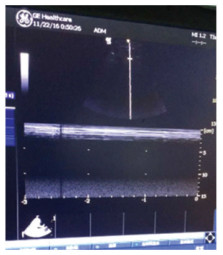

图 4 2016年11月22日床旁超声提示沙滩征。 |

补液消酮、胰岛素控制血糖等对症支持治疗。11月3日患者酮症逐渐好转,但酸中毒进行性加重,最重时血气分析:PH 6.822,PCO2 21.4 mmHg,BE -27.7 mmol/L。最高体温39℃,并伴有患者神志改变,烦躁。左侧腹股沟伤口分泌物首次培养回报革兰阴性(G-)杆菌。予行左侧腹股沟伤口脓肿切开引流、气管插管、有创呼吸机辅助通气及床旁血液净化等ICU多脏器功能支持治疗。11月6日,患者血培养及伤口分泌物再次培养回报:类鼻疽伯克霍尔德氏菌(Burkolderia pseud-omallei, BP)。为求进一步明确,请实验室对患者腹股沟分泌物、血培养分离得到的2株细菌进一步鉴定,确认为同一菌种即类鼻疽伯克霍尔德菌。药敏试验仅对头孢他啶及亚胺培南敏感。两次查血G试验均明显升高,结合患者既往有糖尿病病史,不排外存在侵袭性全身真菌感染可能,治疗方案上调整抗生素为亚胺培南+氟康唑。2周后,患者体温逐渐降至正常,左侧腹股沟伤口愈合良好,血气、感染指标及肺部感染情况较前明显好转(如图 3)。给予降阶梯治疗,调整抗生素为头孢他啶1.5g q6h。21日患者突发胸闷、气促,伴大汗。急诊床旁彩超可见左侧胸膜滑动征消失及沙滩征(如图 4),胸片提示左侧大量气胸(压缩约90%)(如图 2)。11月27日再次出现胸闷气促,胸片提示右侧大量气胸(压缩约90%),治疗上予胸腔闭式引流术、肺复张、机械通气、足疗程抗感染、器官功能维持等。复查胸部CT变化(如图 5)。12月12日患者症状好转,成功撤机,拔除气管导管、转出急诊ICU至急诊观察病区。转出诊断:1.左侧腹股沟皮下脓肿;2.脓毒性休克;3.重症肺炎;4.糖尿病酮症酸中毒;5.多器官功能障碍综合征MODS(ARDS、AKI、DIC);6.双侧液气胸。患者与12月24日好转出院。